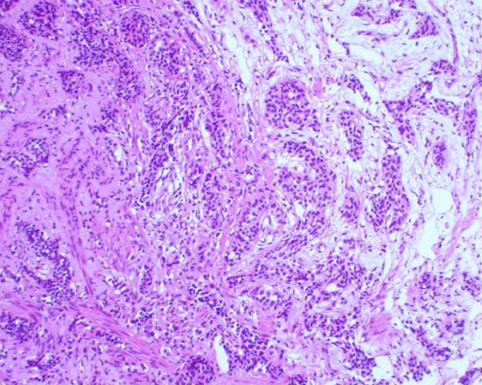

Típico Carcinoide del Colon, con una Depresión Central

[Image-ID:9707]

Tumor Carcinoide/

colon/recto

Micro

15 - 19